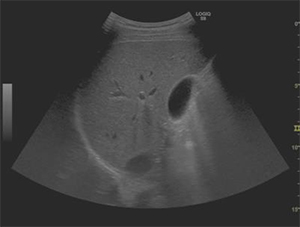

今回発売する「LOGIQ S8 with XDclear」と「LOGIQ E9 with XDclear2.0」は,日野本社で開発された高感度プローブ「XDclearプローブ」の搭載により,体の浅部から深部にいたるまで超音波を届けることが可能になった。腹部一般用の「C1-6-Dプローブ」は,深部の観察範囲を広げることで,体格による画像抽出困難を軽減し,形状が小さいマイクロコンベックスタイプの浅部用「C3-10-Dプローブ」は,血管,小児,腹部など全身のさまざまな部位にあてやすく,表在部の画像の多重エコーなどを解決する。

腹部一般用の「C1-6-Dプローブ」と浅部用の「C3-10-Dプローブ」の搭載により,浅部や深部の画質向上を実現。一台で多様な質の高い検査を可能とする。

画質を左右する超音波診断装置の心臓部であるプローブはこれまで,画像精度を高めると描出できる体内深度が浅くなり,逆に深部まで超音波ビームを届かせようとすると画質が粗くなる相反関係にあった。

同社では,GEヘルスケアの中核開発・製造拠点として,これまで30年以上にわたり世界の医療現場に日本発の先進プローブを届けてきた開発・製造チームの密な連携のもと,プローブの素材を見直し,従来のセラミックに替えて,電気信号と音の変換効率に優れたシングルクリスタル(高密度単結晶)を採用し,これまで使用されていなかった音響エネルギーを有効活用するアコースティックアンプリファイヤー技術,ならびにレンズ表面での温度上昇を抑えてプローブが最大限の性能を発揮できるようにするクールスタック技術を搭載することで,この課題を克服。画質と診断深度の両立を可能にするXDclearプローブの開発で,皮膚に近い表在部から体内深部まで広範囲にわたって均一な高精細画像の描出を可能とした。